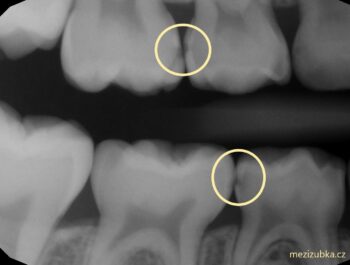

více >>Zachraň mléčnou pětku : 1.díl Mezizubní kazy

Taky se Vám stalo, že dětem čistíte 2 krát denně zoubky, ale zubařka při každé preventivní prohlídce najde zubní kaz? Vtip může být v tom,...